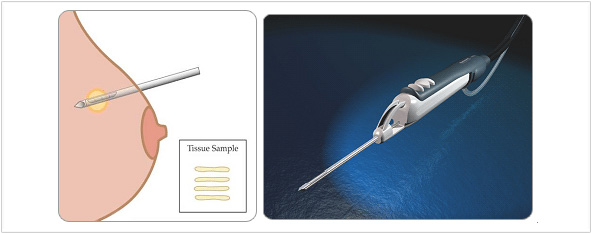

�����˻�

������ ����� ���ϱ� Ȥ�� ���� �ǽ��� ���� �� ������ ���� �Ϻθ� ��� �ڼ��� �����ϴ� ����Դϴ�. ����� ���� ������ ���� ���̶� ���� �� �� ������ ������������ ������ �������� ���ؼ��� �����˻縦 �ؾ߸� ���̶� ������ ������ �˴ϴ�. �̰����� �ڱð�ξ��� 99% Ȯ���� �����մϴ�.